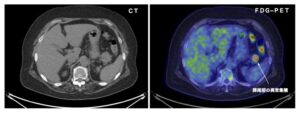

右の画像がその人間ドックで撮影されたFDG−PET画像です。明るい色の部分がFDGの集積している部分であり、膵尾部(膵臓は十二指腸に近いところから順に膵頭部・膵体部・膵尾部に分かれます)に異常集積がみられます。その斜め上にも、二つ、明るい色の部分がありますが、これは腸管内のいわゆる生理的集積であり、異常所見ではないようです。Bクリニックの読影医は、膵尾部の異常集積を、この腸管内の生理的集積と連続したものと考え、膵臓癌を見逃してしまいました。